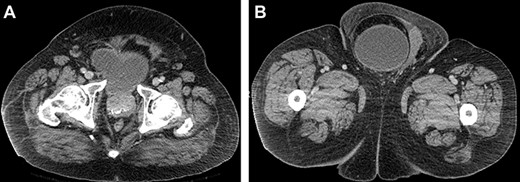

Computed tomography (CT) scan of the abdomen and pelvis with contrast revealed a large right indirect inguinal hernia containing a significant portion of the bladder within the scrotum (Figs 1–3). There was associated bilateral hydronephrosis and hydroureter, and significant scrotal oedema seen within the soft tissues.

(A and B) Axial CT images of the abdomen and pelvis demonstrating the bladder herniating out of the inguinal canal into the scrotum.